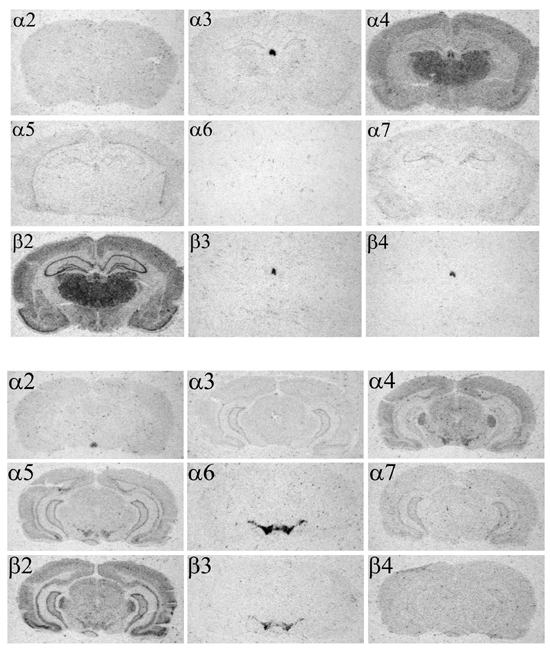

Figure 7.5 : Distribution des ARNms des 9 sous-unités dans le cerveau de rat. En haut, au niveau du thalamus. Le noyau central très marqué par $\alpha $3 et $\beta $4 est l'habénula médiale. En bas, au niveau du mésencéphale. La petite surface ronde marquée par la sonde $\alpha $2 est le noyau interpédonculaire. Les cellules marquées par les sondes $\alpha $6 et $\beta $3 sont les neurones à dopamine de la VTA (au centre) et de la substance noire (les «ailes» latérales). Notez que des marquages différents ne peuvent être directement comparés à cause de la différence d'activité spécifique des sondes et les temps d'exposition (voir le chapitre 5). Au niveau des cellules dopaminergiques, exposées un temps comparable après une hybridation in situ avec des sondes marquées de manière similaire, $\alpha $3 fournirait une image totalement dépourvue de signal et $\alpha $6 une autre totalement saturée. Les corrections à utiliser relativement à $\alpha $2 (coefficients multiplicatifs) sont les suivantes: $\alpha $3=1,9; $\alpha $4=1,0; $\alpha $5=1,1; $\alpha $6=2,9; $\alpha $7=1,8; $\beta $2=1,6; $\beta $3=2,6; $\beta $4=1,2.

ishthalmes

Dans le système nerveux périphérique, $\alpha $4 est exprimée seulement dans le complexe vestibulo-cochléaire [372] (ganglions Scarpa et spiral). En revanche, elle est exprimée à travers tout le cerveau, n'étant absente (ou exprimée à de très faibles niveaux) que dans le striatum, l'hippocampe et le cervelet [335]. Elle est fortement exprimée dans le thalamus et les neurones à dopamine du mésencéphale. $\alpha $3 et $\alpha $5 sont exprimées dans de nombreuses structures du système nerveux à des niveaux différents [335,334]. $\alpha $3 présente une expression particulièrement forte dans l'épithalamus (habénula et glande pinéale) et le noyau du tractus solitaire, mais également à un niveau moindre dans l'hippocampe, le thalamus antérieur et les noyaux moteurs crâniens. $\alpha $6, $\beta $3 et $\beta $4 sont exprimées dans très peu de régions, mais parfois à de très forts niveaux [185,80,90]. Dans le cerveau, $\alpha $6 et $\beta $3 sont présentes en grande quantité dans les neurones catécholaminergiques (noyaux A6, A8-10). Enfin, la sous-unité $\alpha $2 a été principalement détectée dans une région du cerveau de rat, le noyau interpédonculaire, mais également un peu dans le bulbe olfactif [335]. La distribution des ARNms sera abordée de manière plus détaillée au chapitre 12.